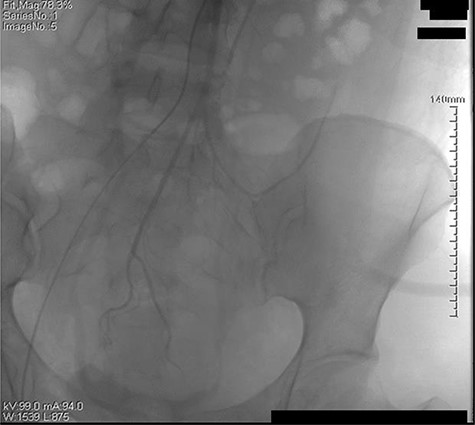

The retroperitoneal hematoma appeared stable and no expanding, also no increase in tension. The hemoglobin concentration reexamination showed no significant change. Considering the bleeding has stopped, the trauma surgeon recommended no further incision for the retroperitoneal hematoma after consultation. Digital subtraction angiography (DSA) was done after operation to further confirm no more artery bleeding. DSA revealed the inferior mesenteric artery and the iliac artery were intact (Figs 2 and 3). The patient was placed in the intensive care unit with a angiographic catheter retained for emergency use. They estimated the total blood loss 1500-2000 ml, 200 ml of fresh frozen plasma and 4 units of packed red blood cells were transfused during operation.

The left iliac artery and inferior mesenteric artery was intact by fluorescence angiography.